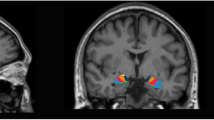

After controlling for the whole-brain gray matter volume and age, the general linear model showed significant reductions in the thickness of right bankssts and inferior parietal cortex as well as the cortical volume of left frontal pole in the patients with SCZ and violence relative to those without violence (Table 2).

The main findings in the present study were that after controlling for the whole-brain volume and age, the SCZ individuals with a history of violence showed reductions in several brain regions involved in emotion and cognition processing, including left frontal pole volume as well as right bankssts and inferior parietal cortical thickness, compared to those without a history of violence. Subsequently, these different brain structures between groups were used to develop the prediction models for violence among SCZ patients using machine learning method. Ultimately, seven predictive models were established. Through comparing with each other, the SVM had the best performance with a balanced accuracy of 0.8231 and an AUC of 0.841.

In the present study, the finding of reduced whole brain volume in patients with SCZ who had a history of violence, compared to those without a history of violence, is in consistence with results of previous studies [25, 26], suggesting the possibility that certain general cognitive impairments associated with whole brain volume reduction are involved into violence. Besides, we also found abnormalities in several regions implicated in the neuropathology of violence, including left frontal pole, right bankssts and inferior parietal regions. Patients with SCZ who had a history of violent behavior displayed decreased gray matter volume in frontal pole in relation to those without violence, which is consistent with another study [27]. This indicates that changes in the prefrontal cortex including the frontal lobe might be involved in the pathophysiology of violent behavior. The prefrontal cortex is thought to play an important role in executive functioning capacity, including regulation of inhibition, emotions and movement. Damage or dysfunction of this area may interrupt the sending of inhibitory inputs to the limbic system, which is composed of hippocampus and parahippocampal gyrus and increases the risk of unregulated behavior [28], speculating that the region can be regarded as structural markers for violence [29]. Temporal lobe is implicated in emotional processing and its abnormalities are linked to the onset of psychosis, hallucinations and delusions in SCZ [30, 31]. Delusions as one of the important features of SCZ have been most consistently related to violent behavior [32]. In addition, the relation of abnormal temporal lobe with violence is also supported by other evidence that alternations in this region can lead to impaired aggression control and increased impulsivity which belong to aspects of characteristic antisocial personality disorder [30, 33]. We also found SCZ subjects with a history of violence displayed decreased cortex thickness in right parietal lobe as a part of the default-mode network (DMN) which is responsible for self-referential and reflective activity as well as attending to internal and external stimuli in relation to those without violence, in consistent with findings from the previous studies [34, 35]. Taken together, the structure volume of the brain is closely associated with the size, density and arrangement of neurons, and its change may lead to the destruction of circuits in relevant brain regions [35], suggesting abnormal neurodevelopment is vital to the neurobiology of violence in schizophrenia.